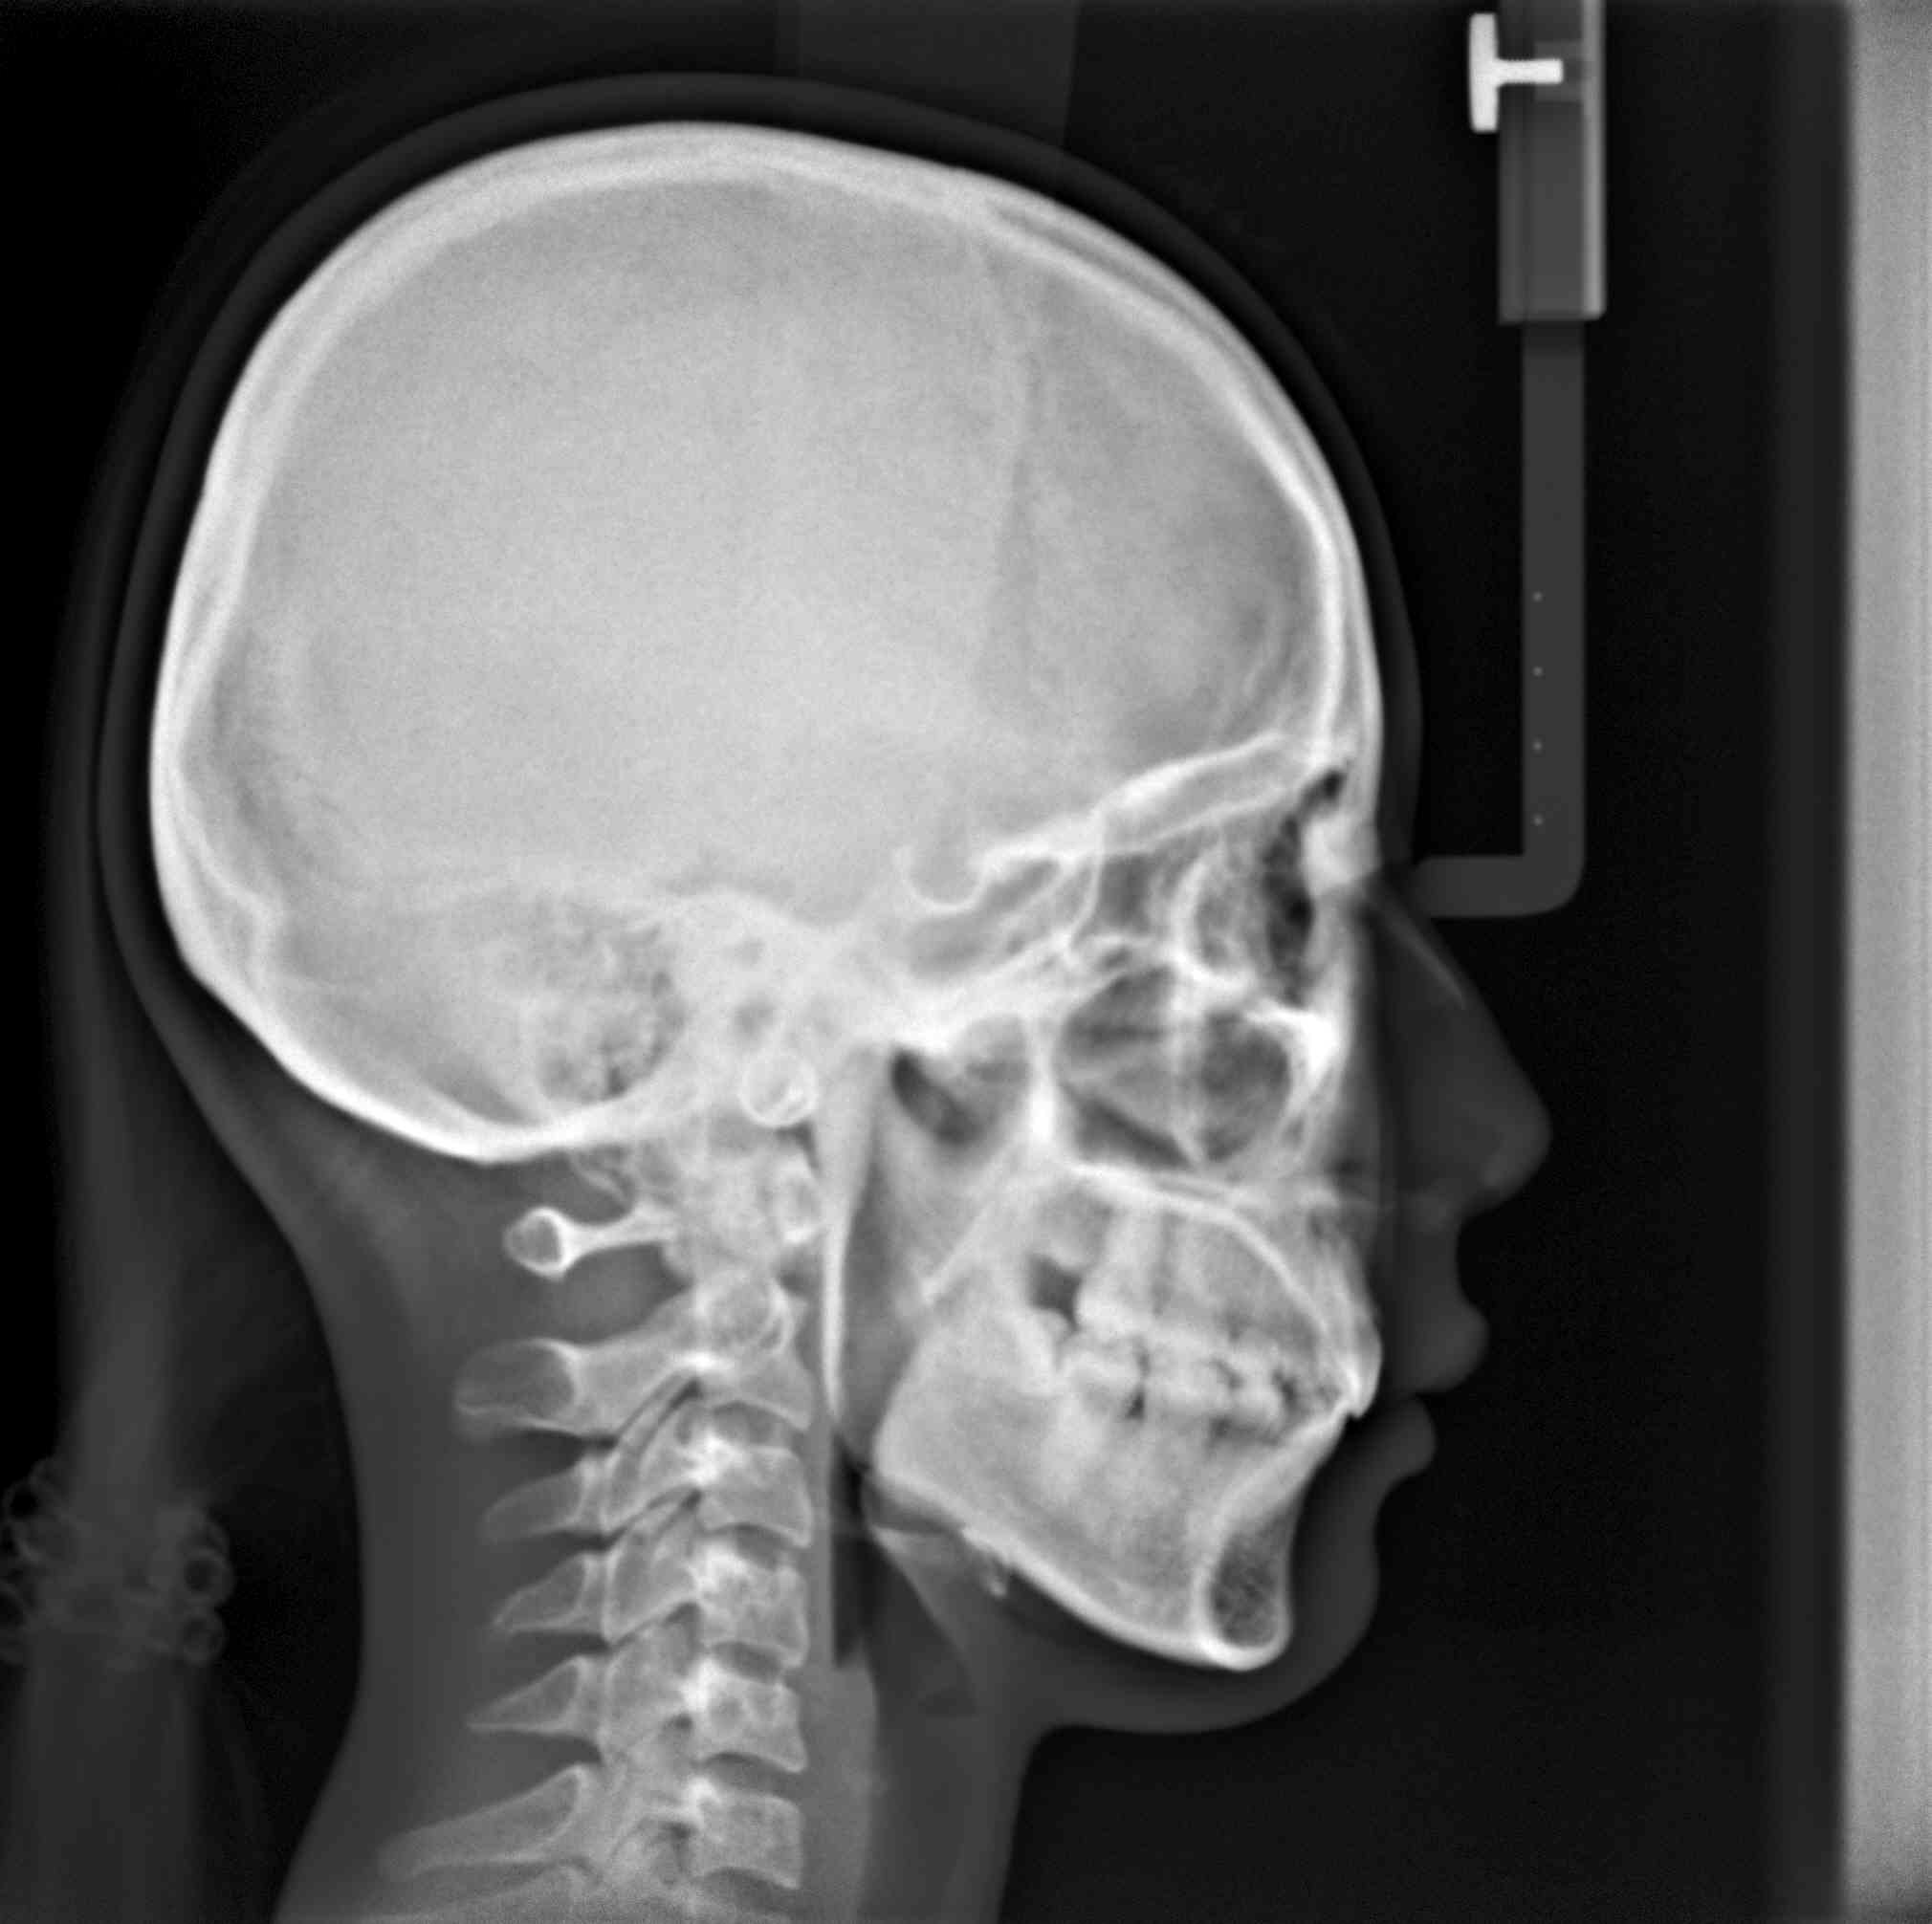

隱適美拔牙改臉型(二) 首頁 案例分享 齒顎矯正 隱適美拔牙改臉型(二) 拔牙改臉型案例 年紀:20 歲 女性 治療方式:隱適美隱形矯正 時間:29個月 主訴:外觀看起來比較暴,希望可以把牙齒排列整齊以及後縮 矯正前 矯正後 矯正前 矯正後 矯正前 矯正後 聲明:本所療程皆由專業醫生評估後,依照個人口腔狀況進行治療。因每位患者個別狀況不同,術後狀況也不盡相同,需親來本所由醫生評估。